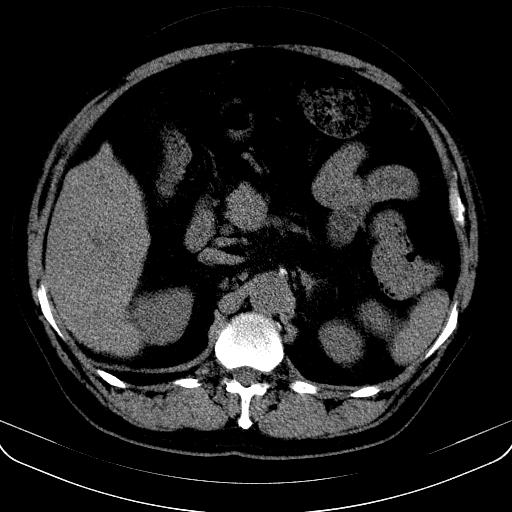

以下是引用jia119在2008-3-5 13:31:00的发言:[br]肝内多发片状低密度影,密度不均,我还是考虑肝ca可能,另肝内小囊肿,胆囊增大。

以下是引用形影不离在2008-3-5 12:18:00的发言:[br]肝硬化伴门脉高压征,肝内占位待排,增强再说.

以下是引用随光逐影在2008-3-5 21:11:00的发言:[br]肝硬化伴门脉高压(食管下段静脉曲张),肝癌不排除。建议:行ct增强扫描检查。

以下是引用同在2008-3-5 13:56:00的发言:[br]考虑肝癌可能性大,胆囊增大.